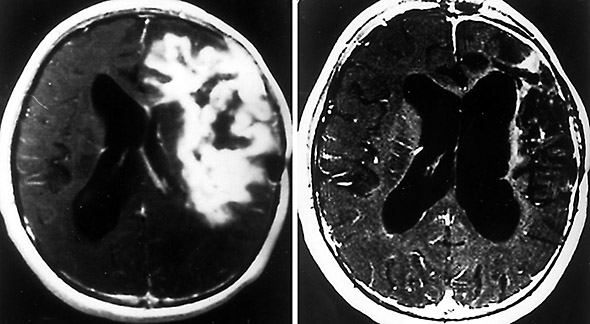

Το MTH-68/H έχει επιτυχία σε ασθενείς με πολύμορφο γλοιοβλάστωμα, που είναι το πιο συχνό και πιο επιθετικό νευροεξωδερμικό νεόπλασμα με κακή πρόγνωση (κατά μέσο όρο επιβίωση έξι μήνες έως ένας χρόνος).

Ο εξασθενημένος ιός της νόσου Newcastle (NDV) με το εμβόλιο MTH-68 / H προκαλεί υποχώρηση διαφόρων όγκων.

Η θεραπεία MTH-68 οδηγεί σε πλήρη ή μερική ύφεση (συρρίκνωση) του όγκου. Πιο συχνά σε προχωρημένο καρκίνο σταθεροποιεί τον όγκο. Ο καρκίνος σταματά να αυξάνεται, όταν μετρείται με διαγνωστικές ιατρικές εξετάσεις, και υπάρχει βελτίωση των συμπτωμάτων.